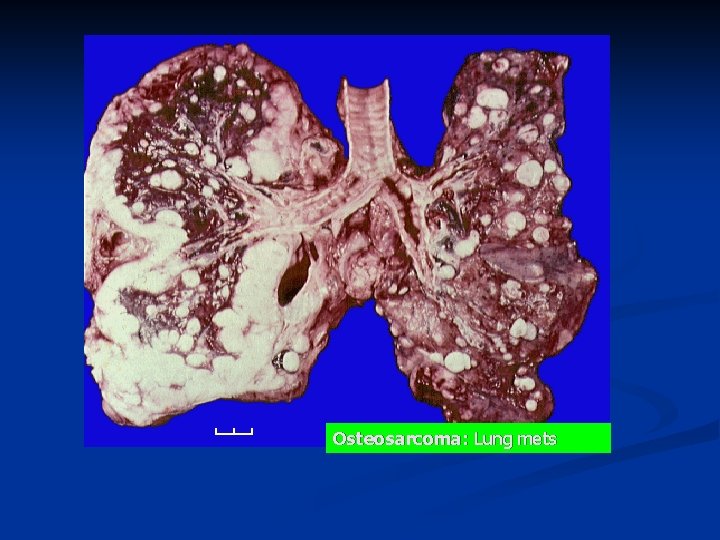

n n Osteosarcoma may occur in any bone The most frequent location is near the knee (~50 -60% of cases) n n n most commonly in the distal end of the femur the upper end of the tibia, upper end of the humerus, pelvis, upper end of the femur. Bone-forming cells produce alkaline phosphatase n The serum alkaline phosphatase is markedly elevated in many patients with osteosarcoma.

Osteosarcoma: Lung mets